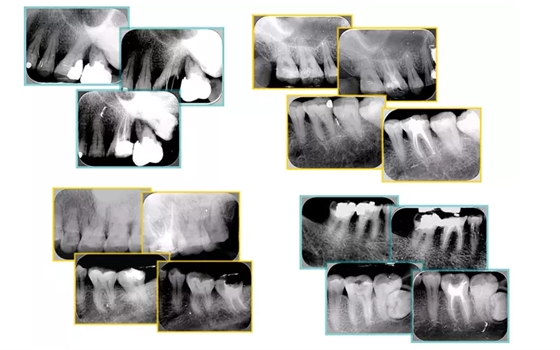

共有 4 張 X 線片,分別是術(shù)前、診斷絲 、主牙膠尖確認(rèn)、術(shù)后。

( 1 )術(shù)前:術(shù)前 X 線片用來了解牙齒的大概情況。術(shù)前預(yù)期為多根牙時(shí) X 線片應(yīng)偏頭拍攝。

( 2 )診斷絲:根據(jù)術(shù)前 X 線片進(jìn)行開髓、根管的初步預(yù)備后,需要插入診斷絲,用來指示工作器械位置。常用 10 號或 15 號擴(kuò)大器作為診斷絲插入牙髓腔。

( 3 )主牙膠尖確認(rèn):通過術(shù)前預(yù)期和診斷絲診斷,明確工作長度、牙根走向,進(jìn)行根管預(yù)備。之后應(yīng)進(jìn)行主牙膠尖(中銼)確認(rèn),已明確根管是否適合充填。

( 4 )術(shù)后:觀察治療效果。

左圖為根管充填術(shù)后 X 線片。圖中可見,根管充填較好。右下圖有白色小點(diǎn),為側(cè)方加壓導(dǎo)致糊劑擠出所致,表明根管充填比較致密。

左圖和上圖為干髓治療后牙齒,齲齒疏通后進(jìn)行根管充填。

如圖為塑化加根充處理后牙齒 X 線片。

常見有修復(fù)性鈣化和增齡性鈣化。下面為根管鈣化 X 線片。

右圖及下圖為器械折斷的 X 線片。箭頭處示折斷器械。

右圖箭頭處示臺階形成。